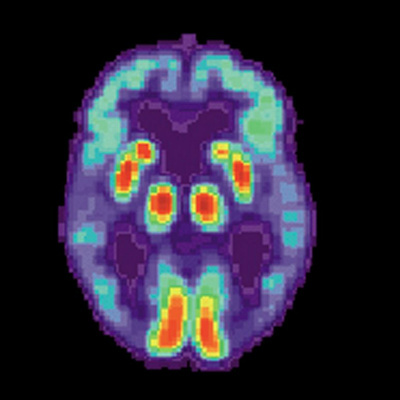

According to the National Institute on Aging, experts estimate that more than five million people in the United States have Alzheimer's disease, a condition that damages memory and cognitive function. David Holtzman - professor and chair of the neurology department at the Washington University School of Medicine, and associate director of the Charles F. and Joanne Knight Alzheimer's Disease Research Center - explains what is happening in the brain of someone with Alzheimer's. He also describes his own laboratory's research into the disease and shares why he believes that it should be treatable. A version of this podcast was first released in our 2012 series on Memory.